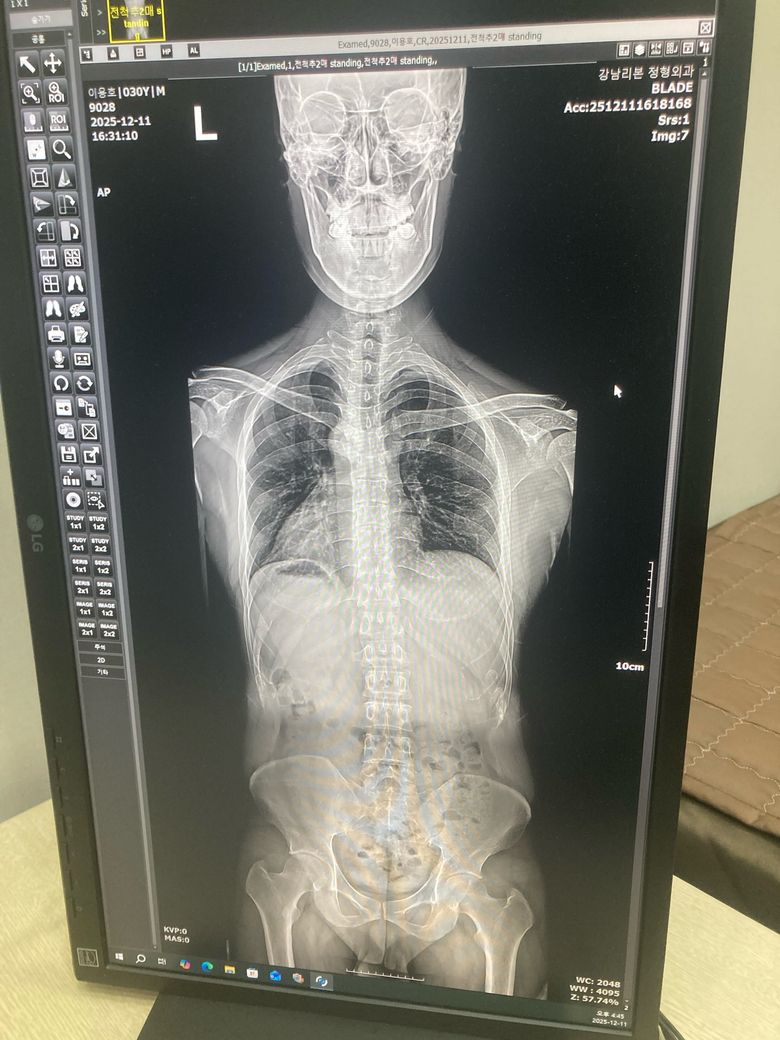

• 1번 째 사진

1번 이 X-ray만으로 "골반 전방경사 여부를 단정하긴 어렵고" 측면에서 보면 "요추전만(허리 커브 증가)은 분명히 보입니다." 전방경사는 임상자세.촉진.측정이 함께 필요해요.

사진으로 보아서는 골반의 틀어짐과 척추측만증, 전방경사, 라운드숄더, 거북목과 일자목등 신체 전반적인 불균형이 있으신 것으로 보입니다.